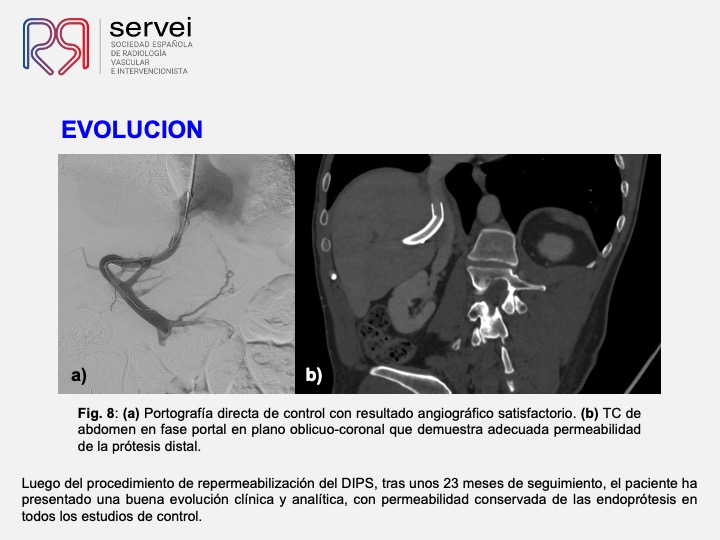

DIPS con técnica de “gun-sight”. Paciente con Síndrome de Budd-Chiari y eventual trombosis protésica

- DIPS tecnica gun-sight 01

- DIPS tecnica gun-sight 02

- DIPS tecnica gun-sight 03

- DIPS tecnica gun-sight 04

- DIPS tecnica gun-sight 05

- DIPS tecnica gun-sight 06

- DIPS tecnica gun-sight 07

- DIPS tecnica gun-sight 08

- DIPS tecnica gun-sight 09

- DIPS tecnica gun-sight 10

- DIPS tecnica gun-sight 11

- DIPS tecnica gun-sight 12

- DIPS tecnica gun-sight 13